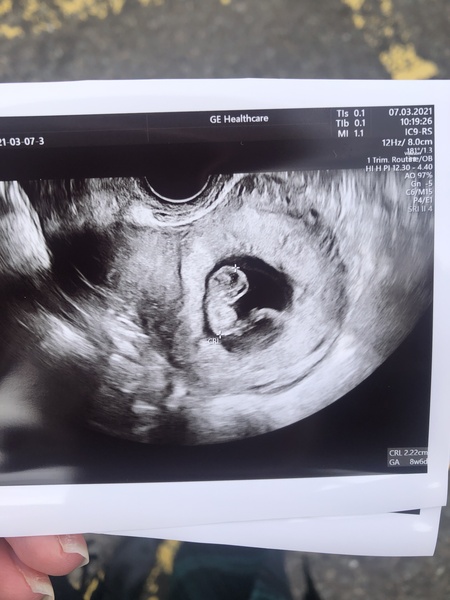

All okay thankfully! Thank you all so much for all the positive vibes, I needed that so so much and I really appreciate it.

Baby measuring 8+6 which is bang on my dates, and she could see a heartbeat and no issues as far as she could see. They’ve actually doubled in size from last Tuesday and look so much more baby like which is crazy.

@PumpkinEvetything how amazing so glad everything went well and what a great picture! ❤

@PumpkinEverything amazing congratulations!! 👏 beautiful scan photo, what brilliant news 🎉

@PumpkinEverything Oh I'm so happy for you! ❤️ And what a beautiful scan photo! I had no idea that's what a scan for those dates would look like. I'm actually excited for mine now! Enjoy the no symptoms - everything is fine.